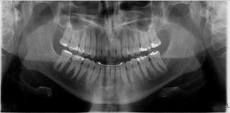

Prvi pregled obavlja ortodont specijalista. Na pregled je neophodno da donesete ortopan snimak (snimak obe vilice). Pregled podrazumeva pregled stanja svih zuba, analizu ortodontskog problema pregledom i analizu ortopan snimka.

Ukoliko se odlučite da kod nas nastavite sa terapijom, dijagnostika mora da se dopuni uzimanjem otisaka za studijske modele, fotografisanjem lica i zuba i još jednim rendgenskim snimkom-profilnim snimkom glave. Na osnovu otisaka, dobijaju se gipsani studijski modeli-replika vaših zubnih lukova. Na tim modelima ortodont vrši precizna merenja i tako dolazi do tačne dijagnoze i mogućnosti za terapijsku proceduru.

Na osnovu sprovedene anamneze, kliničkog i funkcionalnog ispitivanja, analize rendgenskih snimaka, studijskih modela i fotografija, ortodont dobija sve relevantne podatke o ortodontskom problemu jednog pacijenta. Sve te podatke on sklapa u jedinstvenu dijagnozu i odlučuje koji terapijski postupak je najbolji za datog pacijenta.